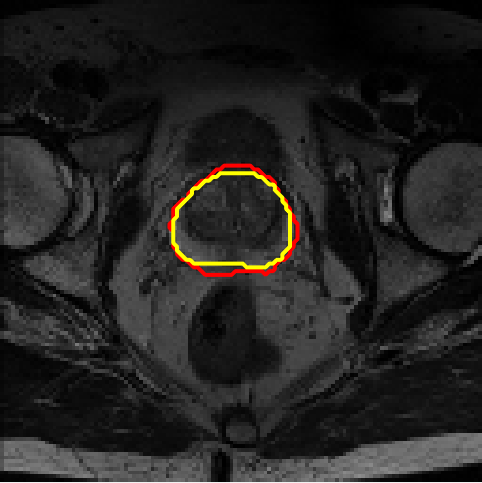

4.4 Results on PROMISE12

We assess different semi-supervised methods on the PROMISE12 dataset (Litjens et al., 2014). The PROMISE12 dataset contains 50 transverse T2-weighted MR images with the most anatomical detail. 35 and 15 cases are randomly selected for training and validation. The images were resized to 128×128128\times 128. The training dataset includes nn fully annotated images, with pixel-wise labels unavailable for the remaining 35n35-n. Table 3 presents the results. Fig. 7 offers a visual comparison of the segmentation results for different models and shows that the proposed method achieves more precise segmentation.

Evaluation on three different datasets indicates that the proposed method achieves the highest segmentation accuracy when the ground truth volumes of unlabeled images are provided to the VP-STD softmax layer (i.e., VP-Netgt), further indicating the importance of volume priors in the structure of semi-supervised segmentation networks.

Figure 7: Example segmentation obtained by different methods on the PROMISE12 dataset. Red lines indicate predicted results, and yellow lines indicate ground truths.